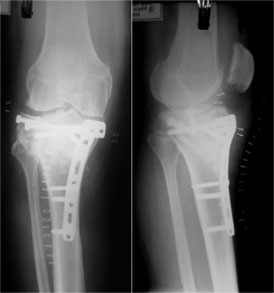

An intra-articular osteotomy was performed. In this procedure the fracture is recreated along the original fracture configuration and then it is fixed in the corrected and desired position. In this instance the fixation was done using Locking Plate (the screws lock with the plate, providing additional hold & stability) and cancellous screws. |